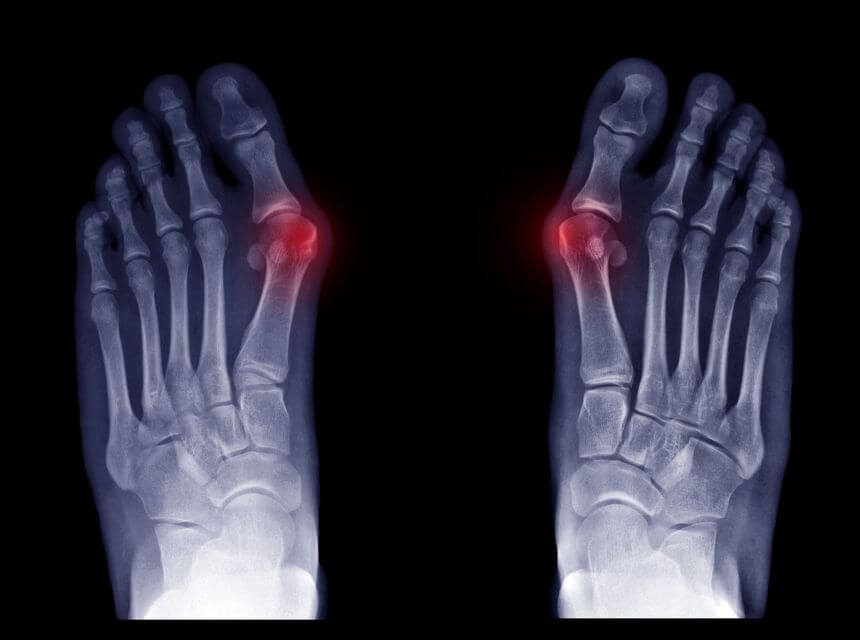

Vbočený palec alebo hallux valgus? Určíte ste už o tom niekde počuli alebo s tým máte rovno nemilú skúsenosť. Pri tomto zdravotnom probléme môžete pociťovať bariéry, ako diskomfort pri chôdzi a ohýbaní prstov, bolestivé obúvanie či tlačenie topánok alebo problém s výberom tej správnej obuvi. Aj to všetko nám môže spôsobovať vbočený palec. Poďme sa bližšie pozrieť na túto, nie len estetickú chybičku krásy spolu s našim novým fyzioterapeutom Bc. Ivanom Bombom.

Inak povedané hallux valgus je jedná z najčastejších deformít chodidla, kedy sa nám prvý článok palca na nohe odchýli smerom dovnútra v tzv. metatarzofalangeálnom kĺbe. Táto deformita palca môže viesť až k prekrytiu druhého prsta alebo k podsunutiu palca pod druhý prst. K vychýleniu palca vedie nesprávna obuv, stuhnutosť a uvoľnenie určitých svalov, ktoré nám navzájom nesprávne spolupracujú. Pri tejto funkčnej poruche môže dochádzať k bolesti celého chodidla, to vedie k vytvoreniu zlého stereotypu chôdze, čo nám ďalej narúša správne postavenie klenby nohy, kolien, bedrových kĺbov a v neposlednom rade aj postavenie panvy a chrbtice. V neskoršom štádiu dochádza k stuhnutiu v kĺbe a ku kostnému výrastku(exostóza).

K príčinám radíme poruchy ako dĺžka palca, väzivová a svalová slabosť, klbová hypermobilita, genetické ochorenia, reumatoídna artritída a neuromuskulárne ochorenia, padnutá klenba (plochonožie) a kladivkové prsty.

Hallux valgus sa v poslednom štádiu pri neustupujúcich bolestiach rieši chirurgicky.